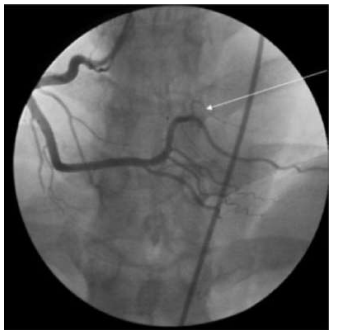

Em pacientes com infarto com supara de ST inferior, com oclusão da coronária direita e seus ramos, encontramos com certa frequência bloqueios avançados.

Qual é a artéria assinalada na seguinte figura, considerando essa incidência oblíqua anterior esquerda?

Enunciado 3413087-1